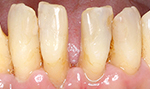

初診で前歯の保険の差し歯が変色し形も色も悪いのでセラミックで治したいと希望した患者さんです。

術後

患者さんは女性で柔らかい感じにしたいと希望がありましたので少し丸みをだして作りました。患者さんは満足しております。

術後4年経過

タバコを吸う方ですが歯の色の変色や着色また歯肉退縮もなく歯垢の付着もありませんでした。

術前

後前

4年後